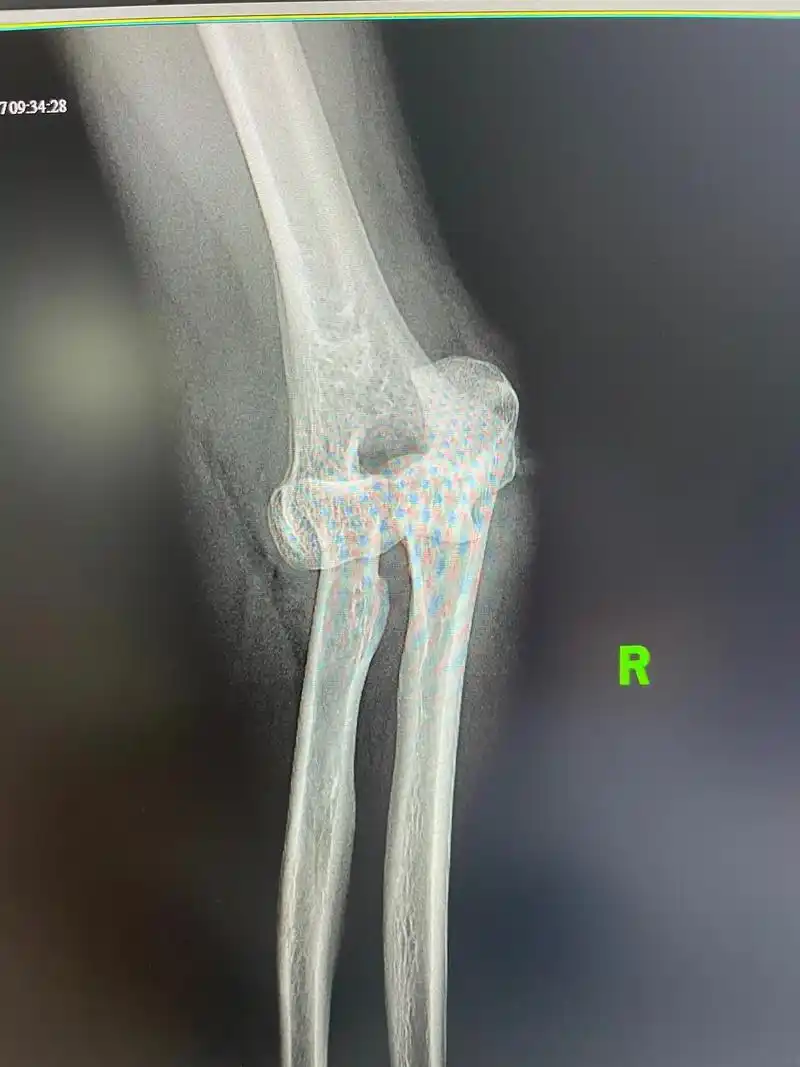

急性肘关节脱位的6种手法复位方法

医学影像 肘关节脱位,闭合复位.看看还有什么问题? - 抖音